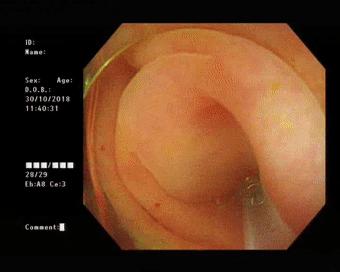

患者做好肠道准备后于30日上午在内镜室进行了内镜下逆行阑尾炎治疗术。电子结肠镜到达回盲部, 进入盲肠,可见:阑尾开口呈半月形,边缘粘膜充血、水肿,诊断考虑“急性阑尾炎”。随后,在斑马导丝引导下将取导管引导入阑尾腔用生理盐水进行阑尾腔反复冲洗可见乳白色脓液涌出,见脓液流尽用,并用替硝唑保留阑尾灌注,退镜,患者自诉腹痛明显缓解。

(镜下可见)